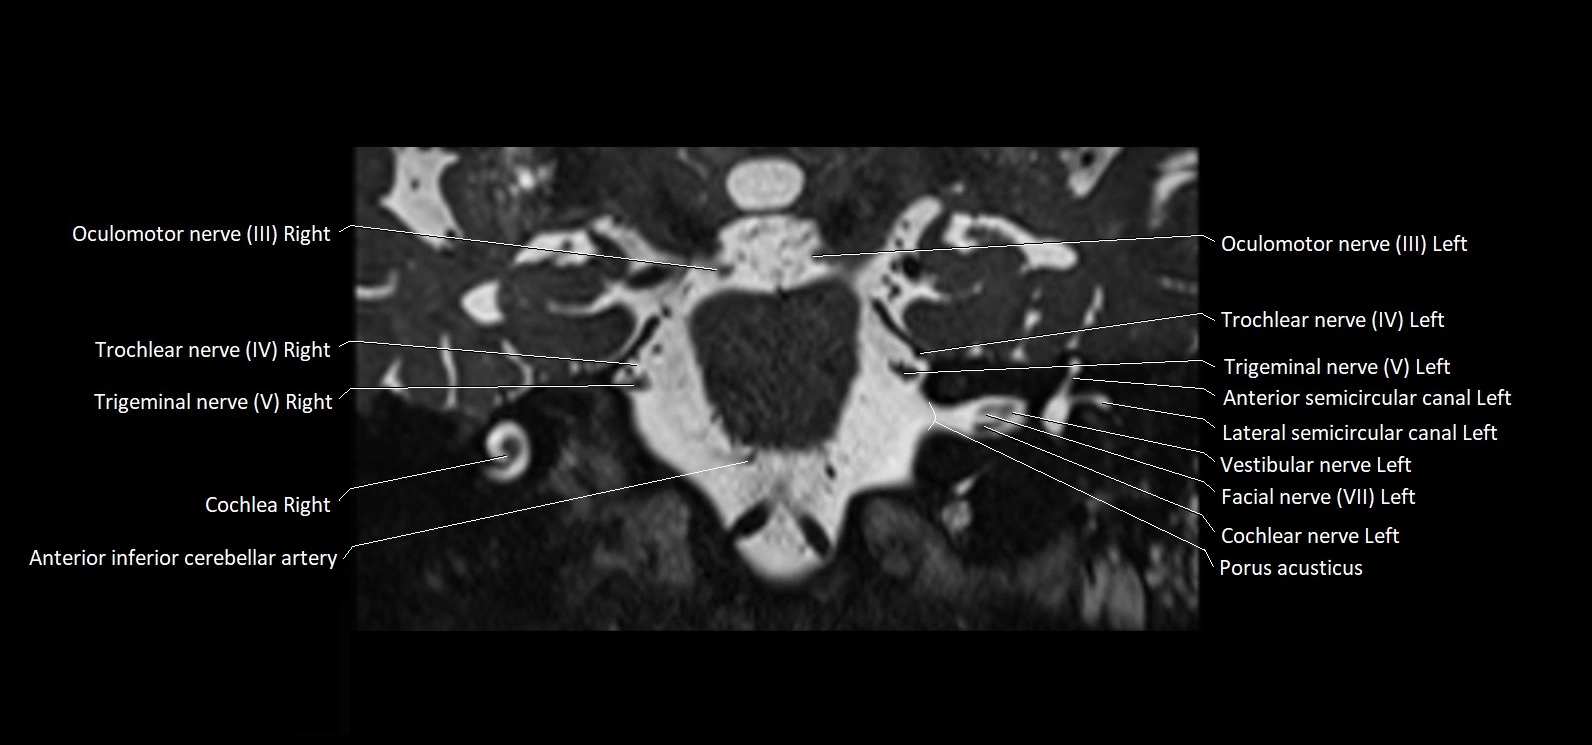

MRI Appearance

• The abducens nerve is a small, thin, linear structure

• Best visualized on high-resolution T2-weighted 3D MRI sequences (e.g., FIESTA or CISS)

• Seen as a hypointense (dark) line running from the brainstem at the pontomedullary junction, traversing the prepontine cistern, and entering Dorello’s canal under the petrosphenoidal ligament, then into the cavernous sinus, and finally the orbit

• May be challenging to visualize in standard MRI due to its small size

• Pathology may be inferred by absence, displacement, or enhancement of the nerve

MRI images

image